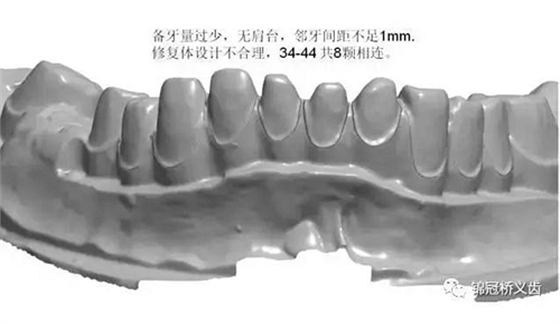

1、臨床備牙不合理或基牙條件不適合做氧化鋯

如:無肩臺(tái)、凹面肩臺(tái)、邊緣線不清晰、雙重邊緣線、備牙空間不足、基牙有倒凹或牙橋沒有共同就位道、基牙切端或頜緣過于尖銳等等。